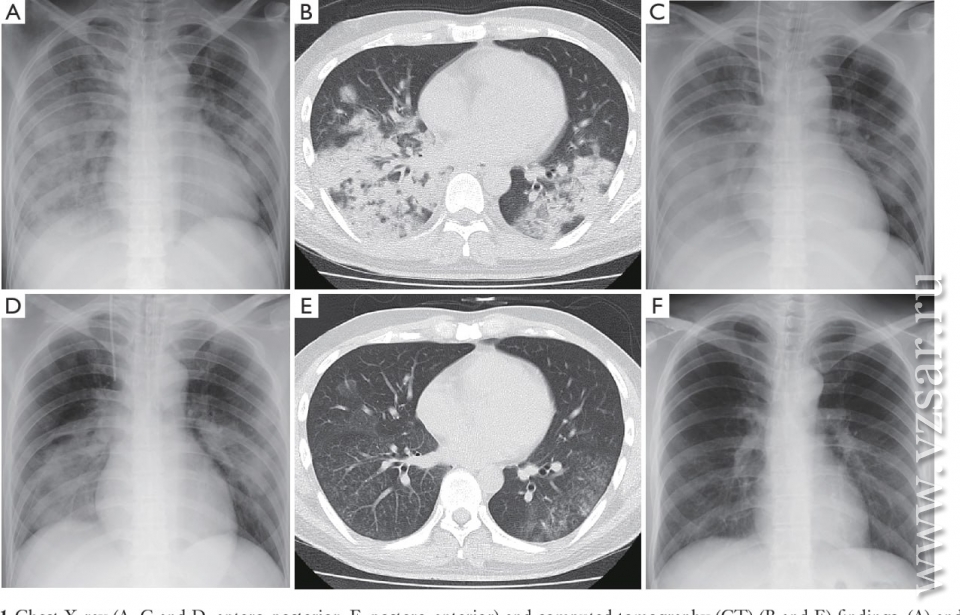

Кроме того, Грайфер сообщил, что в регионе растет количество случаев заболевания микоплазменной пневмонией (разновидность атипичной пневмонии).

"Если раньше она регистрировалась у людей со сниженным иммунитетом, то сейчас этот вид пневмонии фиксируется и у здоровых людей", - констатировал спикер.